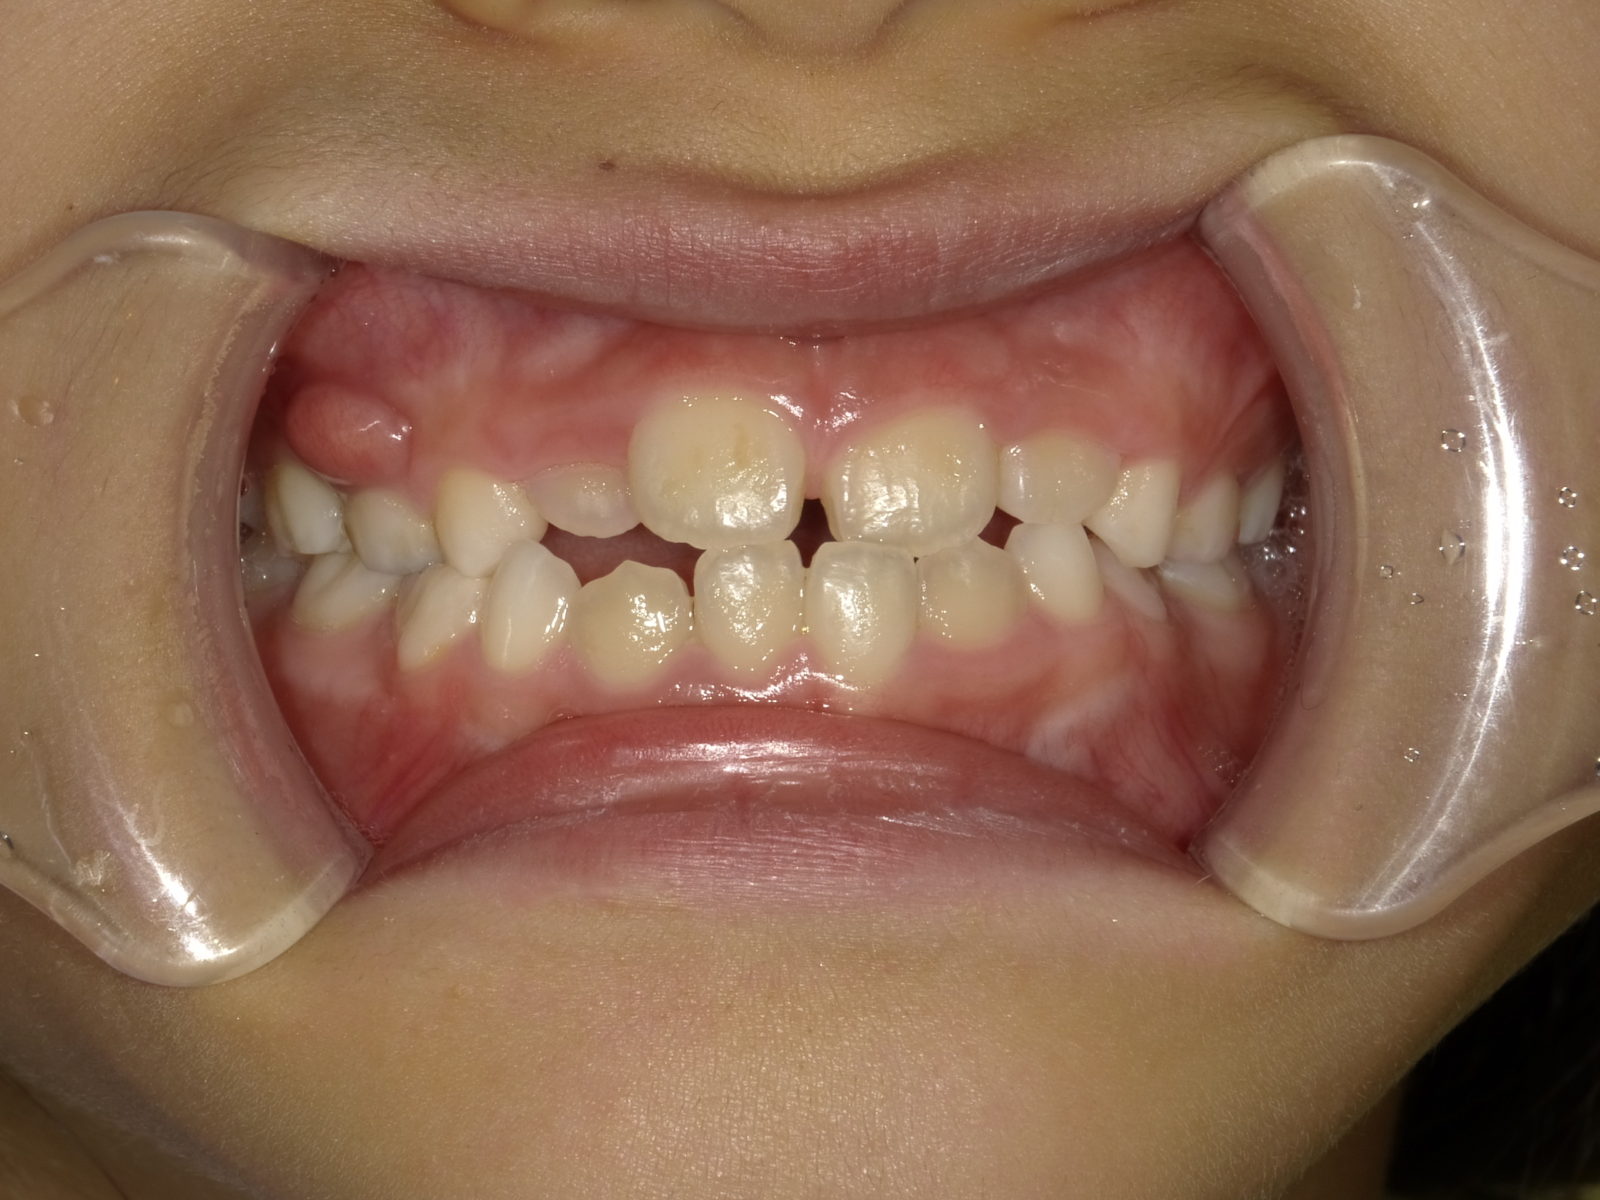

顎顔面矯正の説明をする前に、「なぜ子供の歯並びが悪くなるの?」に関してお答えします。

簡単にお伝えすると、歯が生える土台の「顎」が昔と比べて小さくなっているためです。

狭い顎に無理矢理歯が並ぼうとするので、ガチャガチャになるのです。

理想的には、6~7歳の頃に矯正治療を開始することが望ましいとされています。特に、反対咬合(受け口)の症状を持つお子さんの場合、4~5歳から治療を始めることで、治療結果の質が大きく向上します。反対咬合を放置すると、成人後に外科的な処置が必要となる場合もありますので、早期治療が重要です。